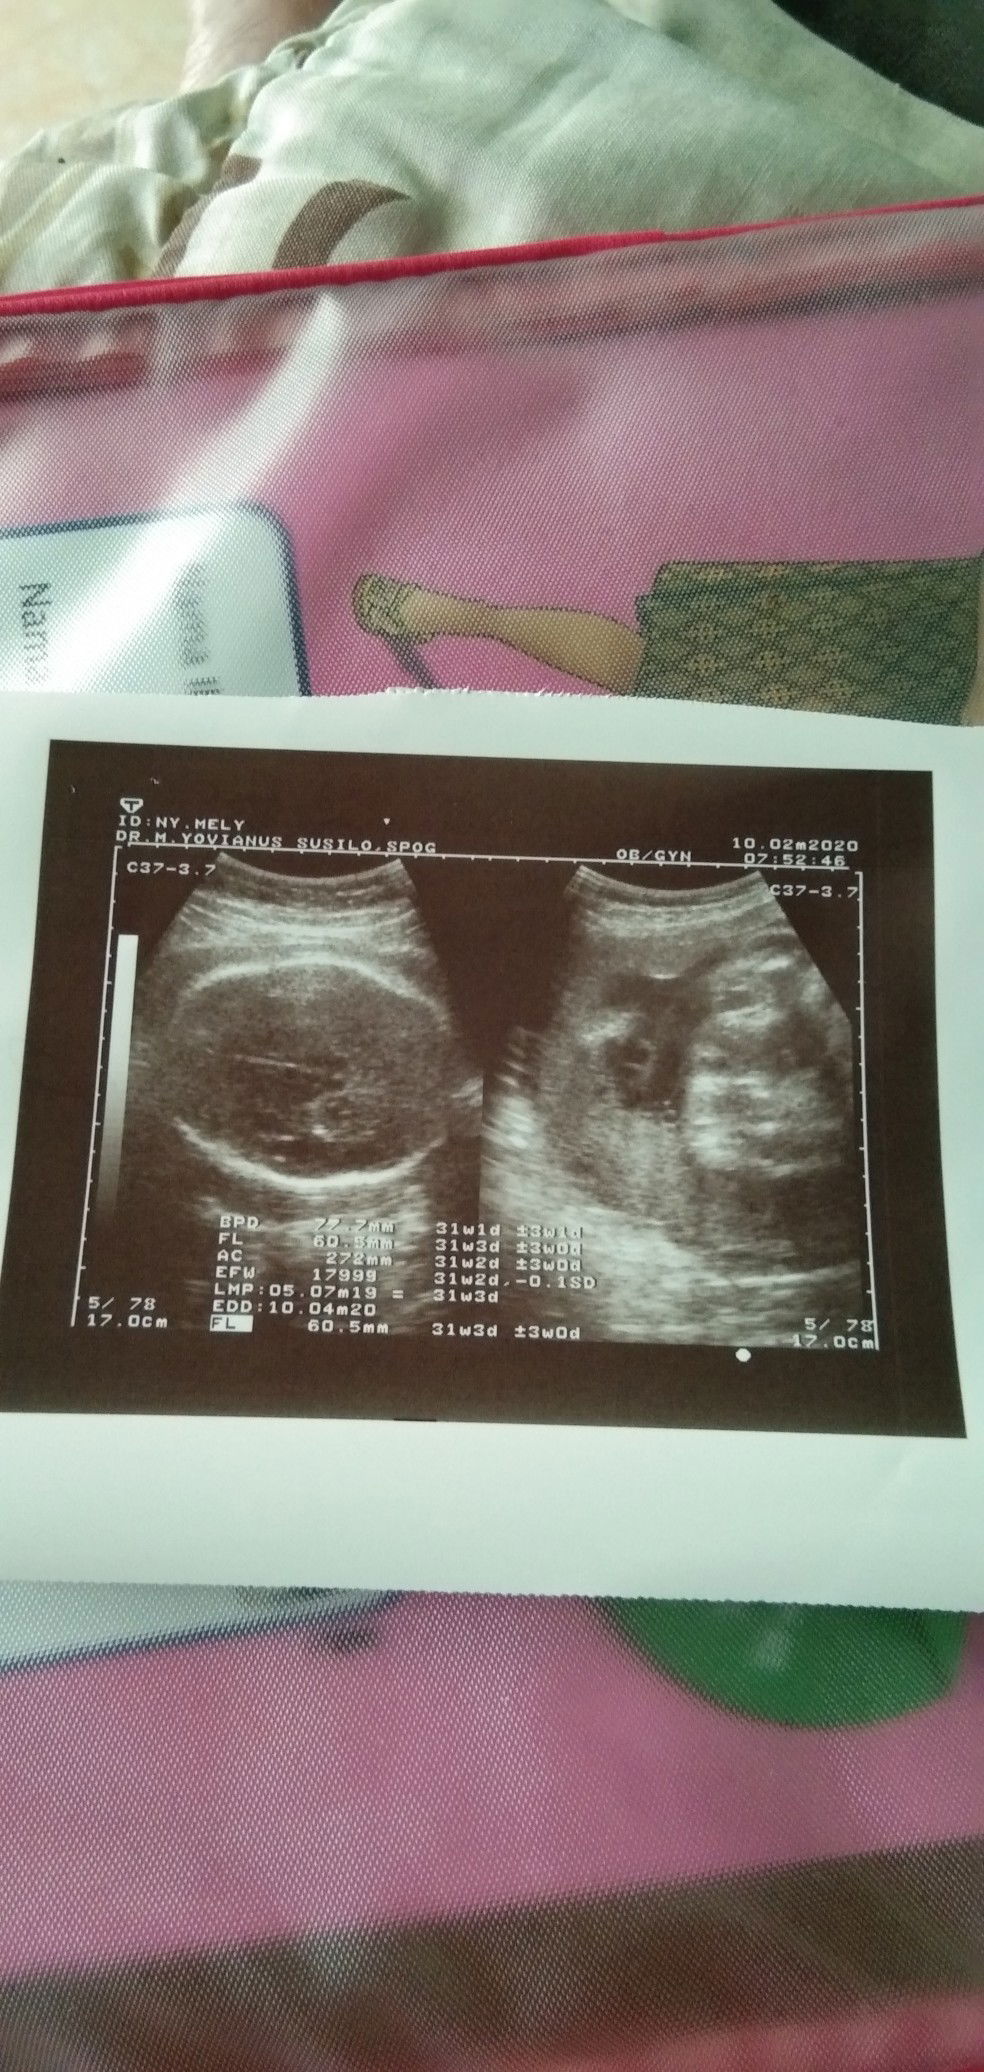

panjang bayi

Bunda... Mau tanya ,kalau panjang bayi nya berapa yaa ...saya lupa tadi gak nanyain dokter